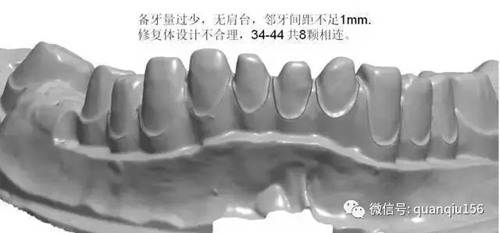

1、臨床備牙不合理或基牙條件不適合做氧化鋯

如:無肩臺(tái)、凹面肩臺(tái)、邊緣線不清晰、雙重邊緣線、備牙空間不足、基牙有倒凹或牙橋沒有共同就位道、基牙切端或頜緣過于尖銳等等。